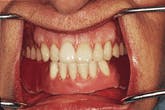

Figure14-The completed maxillary denture and the implant-retained mandibular denture.

Figure 14